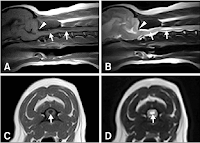

Dr. Roque Antonio de Almeida junior , lesão medular em cães